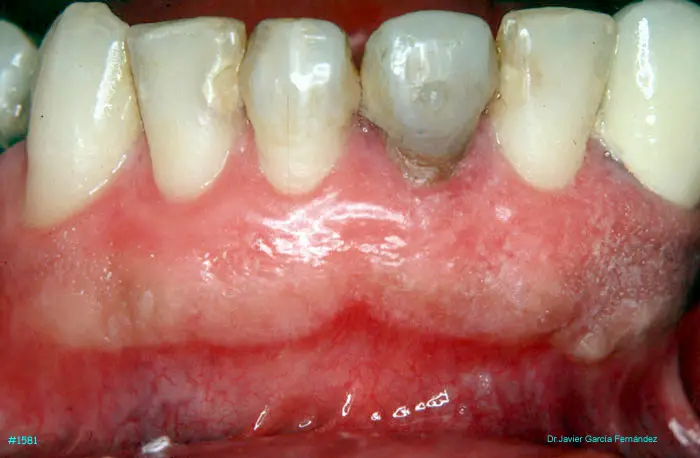

Atlas of Surgical Techniques in Periodontics. Chapter IV. Atlas de Técnicas Quirúrgica en Periodoncia

image 106